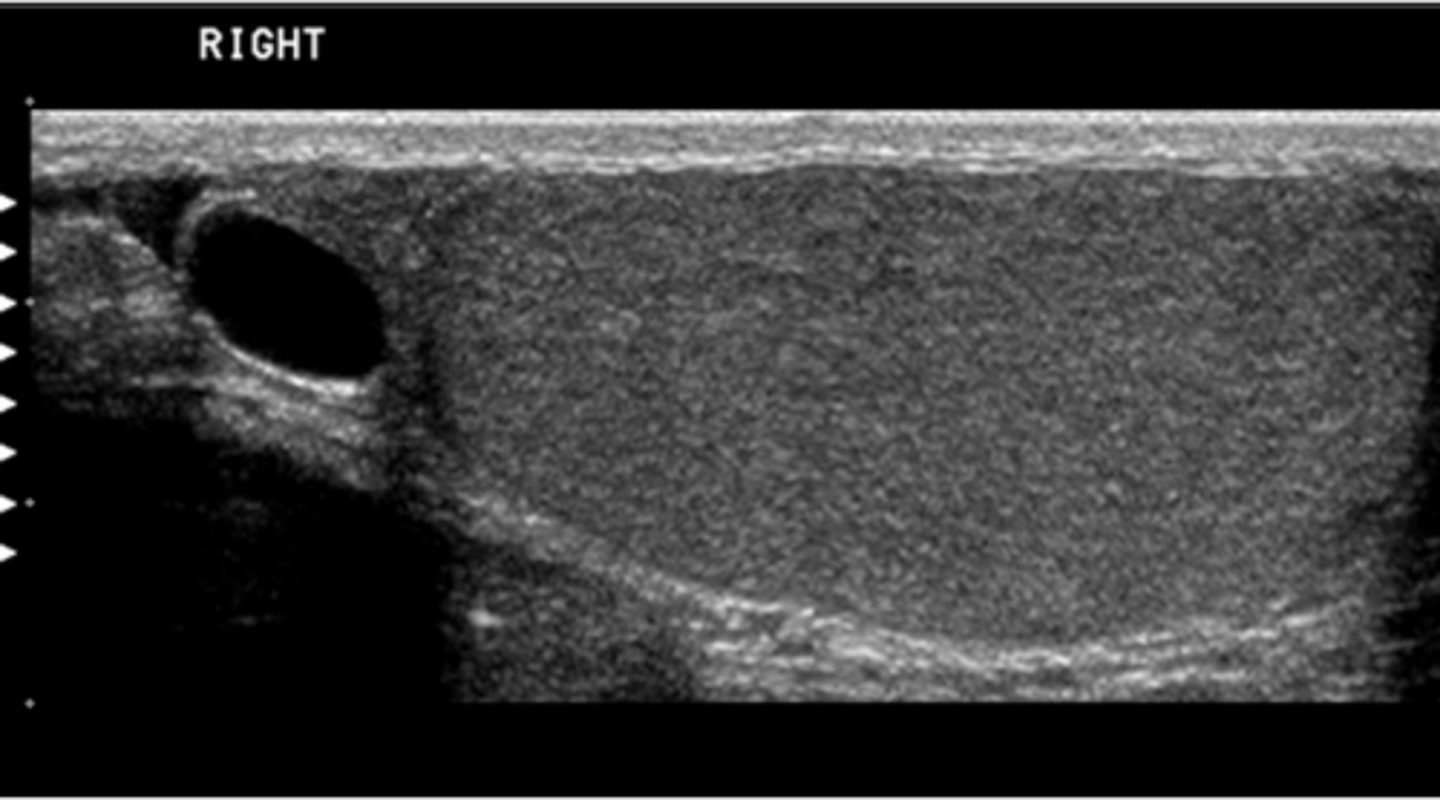

d. fusiform

You are asked to perform a follow-up study on a patient with a known abdominal aortic aneurysm. Which of the following terms correctly describes this aneurysm?

a. pseudoaneurysm

b. saccular

c. dissecting

e. dumbbell

b. b

Which of the following shows the correct plane for measuring the diameter of this aortic aneurysm?

a. a

c. c

d. d

e. both b and c are correct